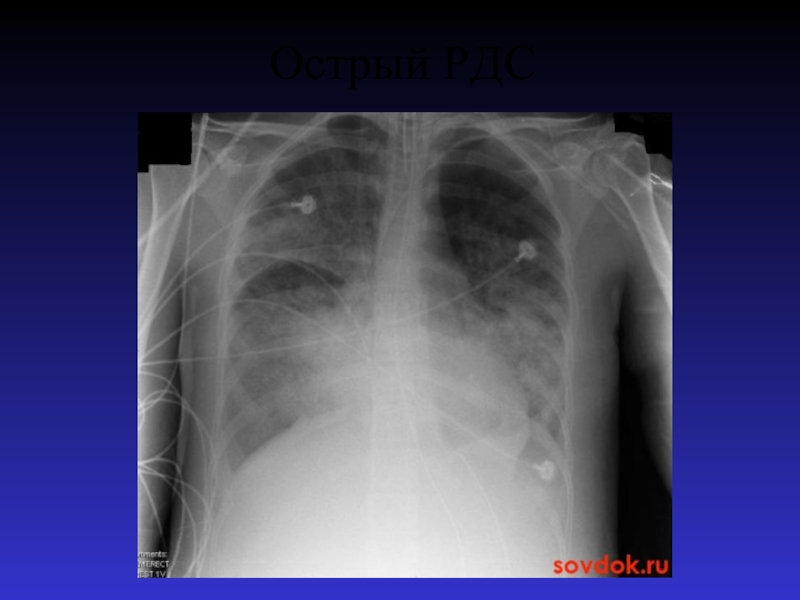

Слайд 56Острый РДС

Слайд 51Острый респираторный дистресс-синдром (некардиогенный отек легких

взрослых - тяжёлая форма дыхательной недостаточности, характеризующаяся

специфическими изменениями в лёгких

- диффузной инфильтрацией, сопровождающейся некардиогенным отёком,

альвеолярным коллапсом,

острой дыхательной недостаточностью.

Несмотря на различие этиологических факторов, они прямо или косвенно воздействуют на лёгкие, вызывая повреждение лёгочных структур. Главным признаком синдрома является гипоксемия, отражающая несостоятельность транспорта кислорода в лёгких.